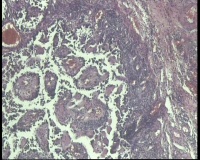

| 性别 | 女 | 年龄 | 53岁 | 临床诊断 | 右侧卵巢囊肿 |

| 一般病史 | 彩超:盆腔可见囊实性回声,囊性为主,大小约5.0x3.7厘米,其内可见分隔回声,部分分隔内回声不纯净,形态欠规整 | ||||

| 标本名称 | 腔镜下右侧卵巢囊肿手术 | ||||

| 大体所见 | 囊壁样组织5.5x5.0厘米,4.5x2.5厘米2块,壁厚0.1-0.2lm,囊壁大部分光滑,局灶见0.7x0.5x0.3厘米淡黄色突起组织,另见淡黄色、肉粉色质软组织2.8厘米一堆。 | ||||